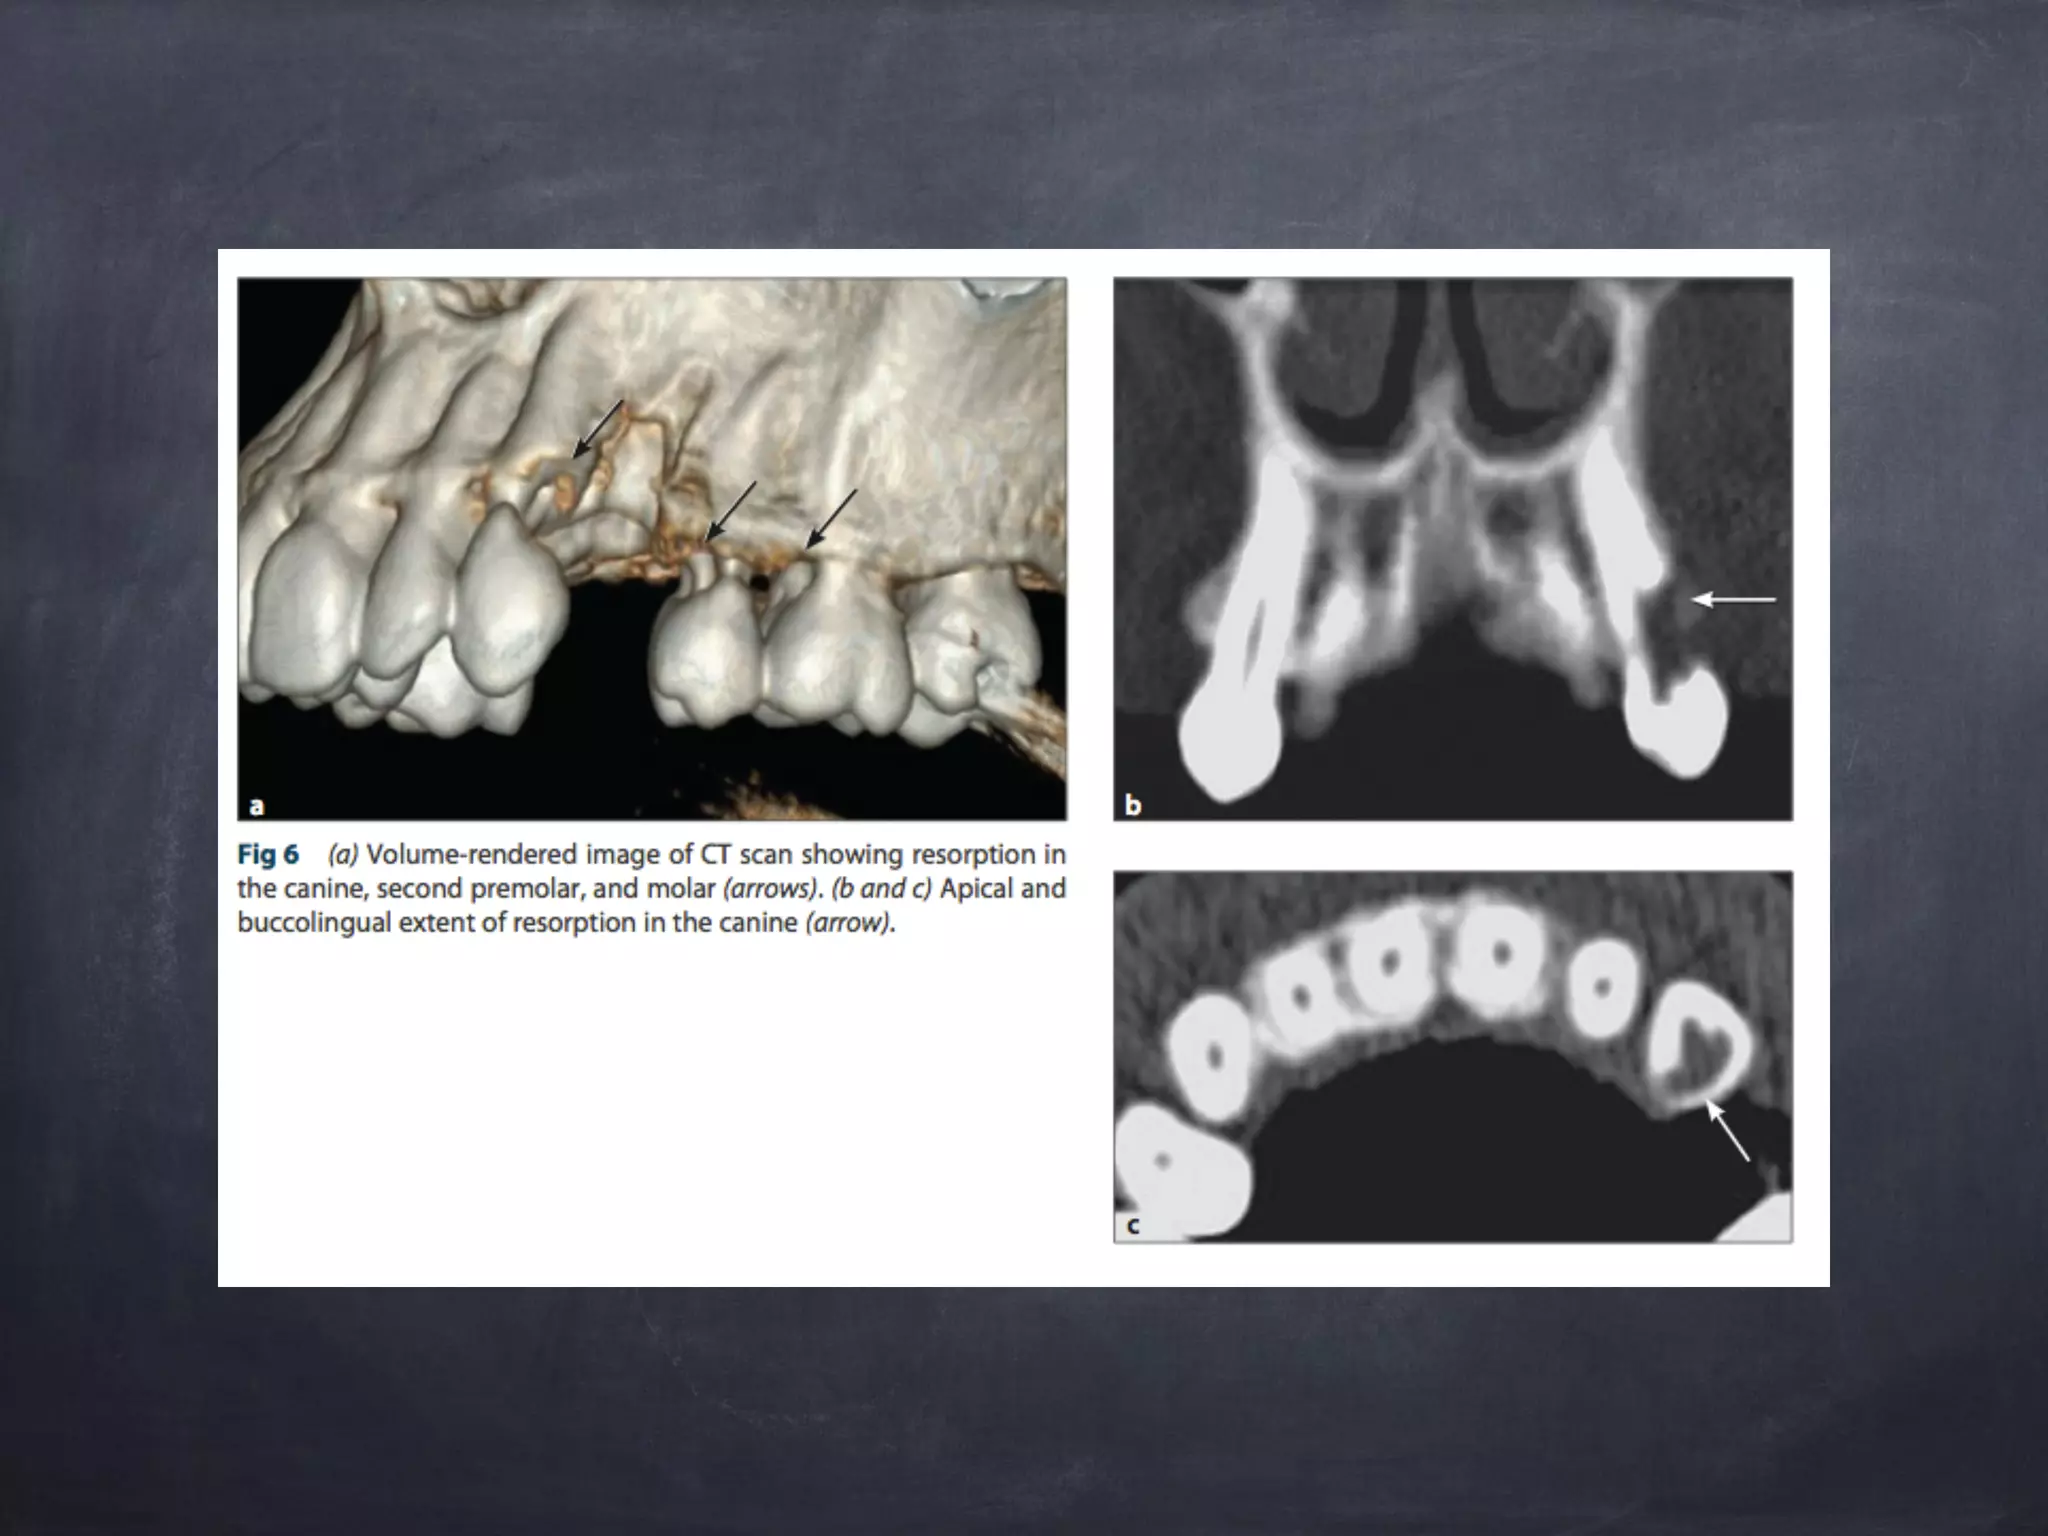

Cone beam CT